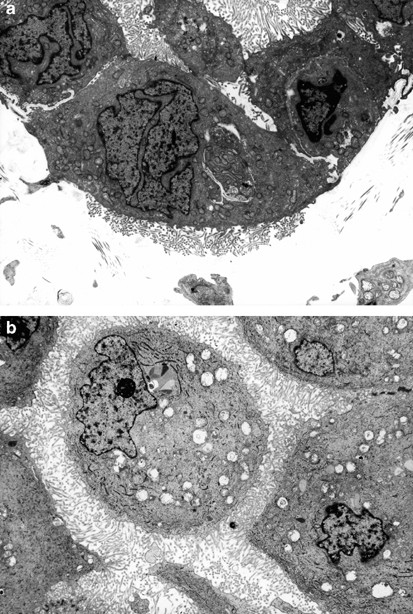

In the serous carcinomas, microvilli were present only on the luminal or papillary surfaces. They were usually straight, varied in length, and were fewer in number than in the mesotheliomas (Figures 10a and 11). The cell membranes were closely apposed and sometimes appeared to be interdigitating, especially in the low-grade tumors (Figure 12). Multiciliated cells were occasionally seen in some of the low-grade serous tumors, and a large number of microvilli were distributed between the cilia on the surface of these cells (Figure 10a, b). A few or a single cilium were often found in the higher-grade serous carcinomas, but, in general, these structures tended to be less common in the less-differentiated tumors (Figure 13). Small bundles of intermediate filaments were only rarely identified in the cytoplasm of three cases.

(a) Electron micrograph of a serous carcinoma. The cell membranes are closely apposed. The apical cell surface of some cells are covered by microvilli. A ciliated cell can be seen in the right upper corner of the figure. (b) Higher magnification of a ciliated cell of the same tumor as shown in (a). In addition to the cilia, the cell membrane appears to be covered by many microvilli, which exhibit a great variation in their lengths (a, × 5500; b, × 23 000).

Same case as shown in Figure 12, showing several poorly developed cilia on the surface of one of the cells (× 10 000).

In all of the cases in which electron microscopy studies were performed, this technique allowed the differential diagnosis to be clearly established between epithelioid mesothelioma and serous carcinoma. The mesotheliomas were characterized by a profusion of long, slender, wavy microvilli occurring along any of the surfaces of the cells. This is in contrast to the serous carcinomas in which the microvilli were less numerous, and straight, and, although they were of varying lengths, they were in general shorter and confined to the luminal and papillary surfaces. Additionally, the cell membranes in the serous carcinomas were intimately apposed, while, in the mesotheliomas, intercellular gaps that often exhibited microvilli were a common finding. Similar to previous ultrastructural studies, large collections of intermediate filaments arranged in tonofibrillar bundles and intracytoplasmic lumens covered by microvilli were common findings in mesotheliomas,65, 66, 67 but not in serous carcinomas.68, 69, 70 No intracytoplasmic lumens were identified in any of the serous carcinomas investigated, and only rare small bundles of intermediate filaments were found in a few cases. Another finding that was helpful in distinguishing serous carcinomas from mesotheliomas was the presence of multiciliated cells in serous carcinomas, but not in mesotheliomas. Multiciliated cells, such as those shown in Figure 10a and b, have previously been reported in serous carcinomas and are more often found in low-grade serous carcinomas and serous tumors of borderline malignancy originating in the ovary and peritoneum.23, 24, 69, 70, 71, 72 Neither in the present study nor in previous investigations have these cells been found in mesotheliomas. Cells presenting a solitary cilium or a few cilia have frequently been found in serous carcinomas, including those of high-grade malignancy; however, their occurrence in mesotheliomas is exceedingly rare.73, 74